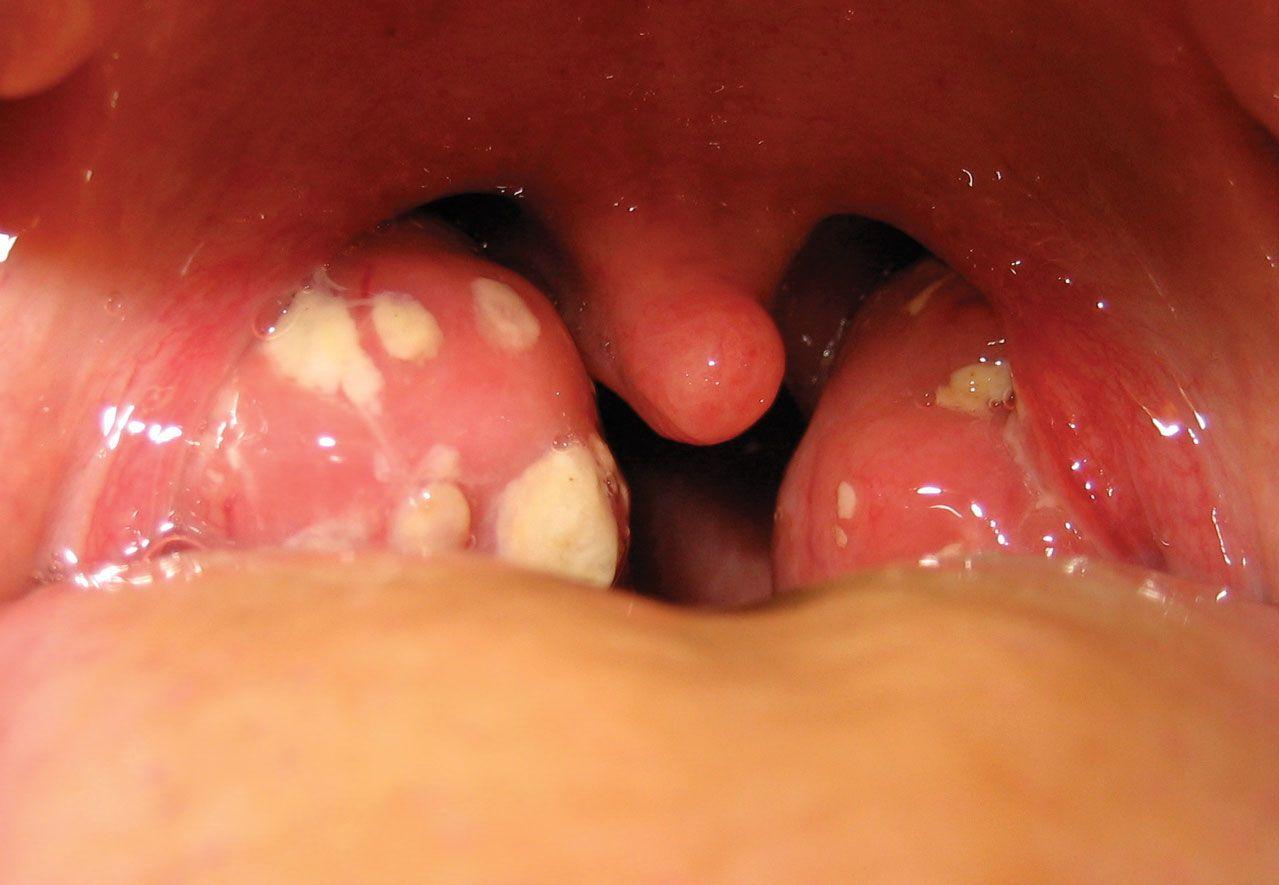

Viêm amidan cấp thường gặp ở trẻ từ 3 – 4 tuổi trở lên và có xu hướng khởi phát đột ngột. Niêm mạc amidan trong giai đoạn này bị xung huyết, đỏ rực và sưng to. Bề mặt amidan có thể tiết dịch nhiều hơn bình thường, đây là dấu hiệu viêm amidan rất điển hình ở giai đoạn đầu.

- Amidan xuất hiện các mảng trắng hoặc vàng

- Amidan sưng đỏ, có thể xuất hiện mảng trắng hoặc mủ

- Mức độ sưng viêm của amidan

- Sự xuất hiện của mủ, dịch tiết, mảng trắng